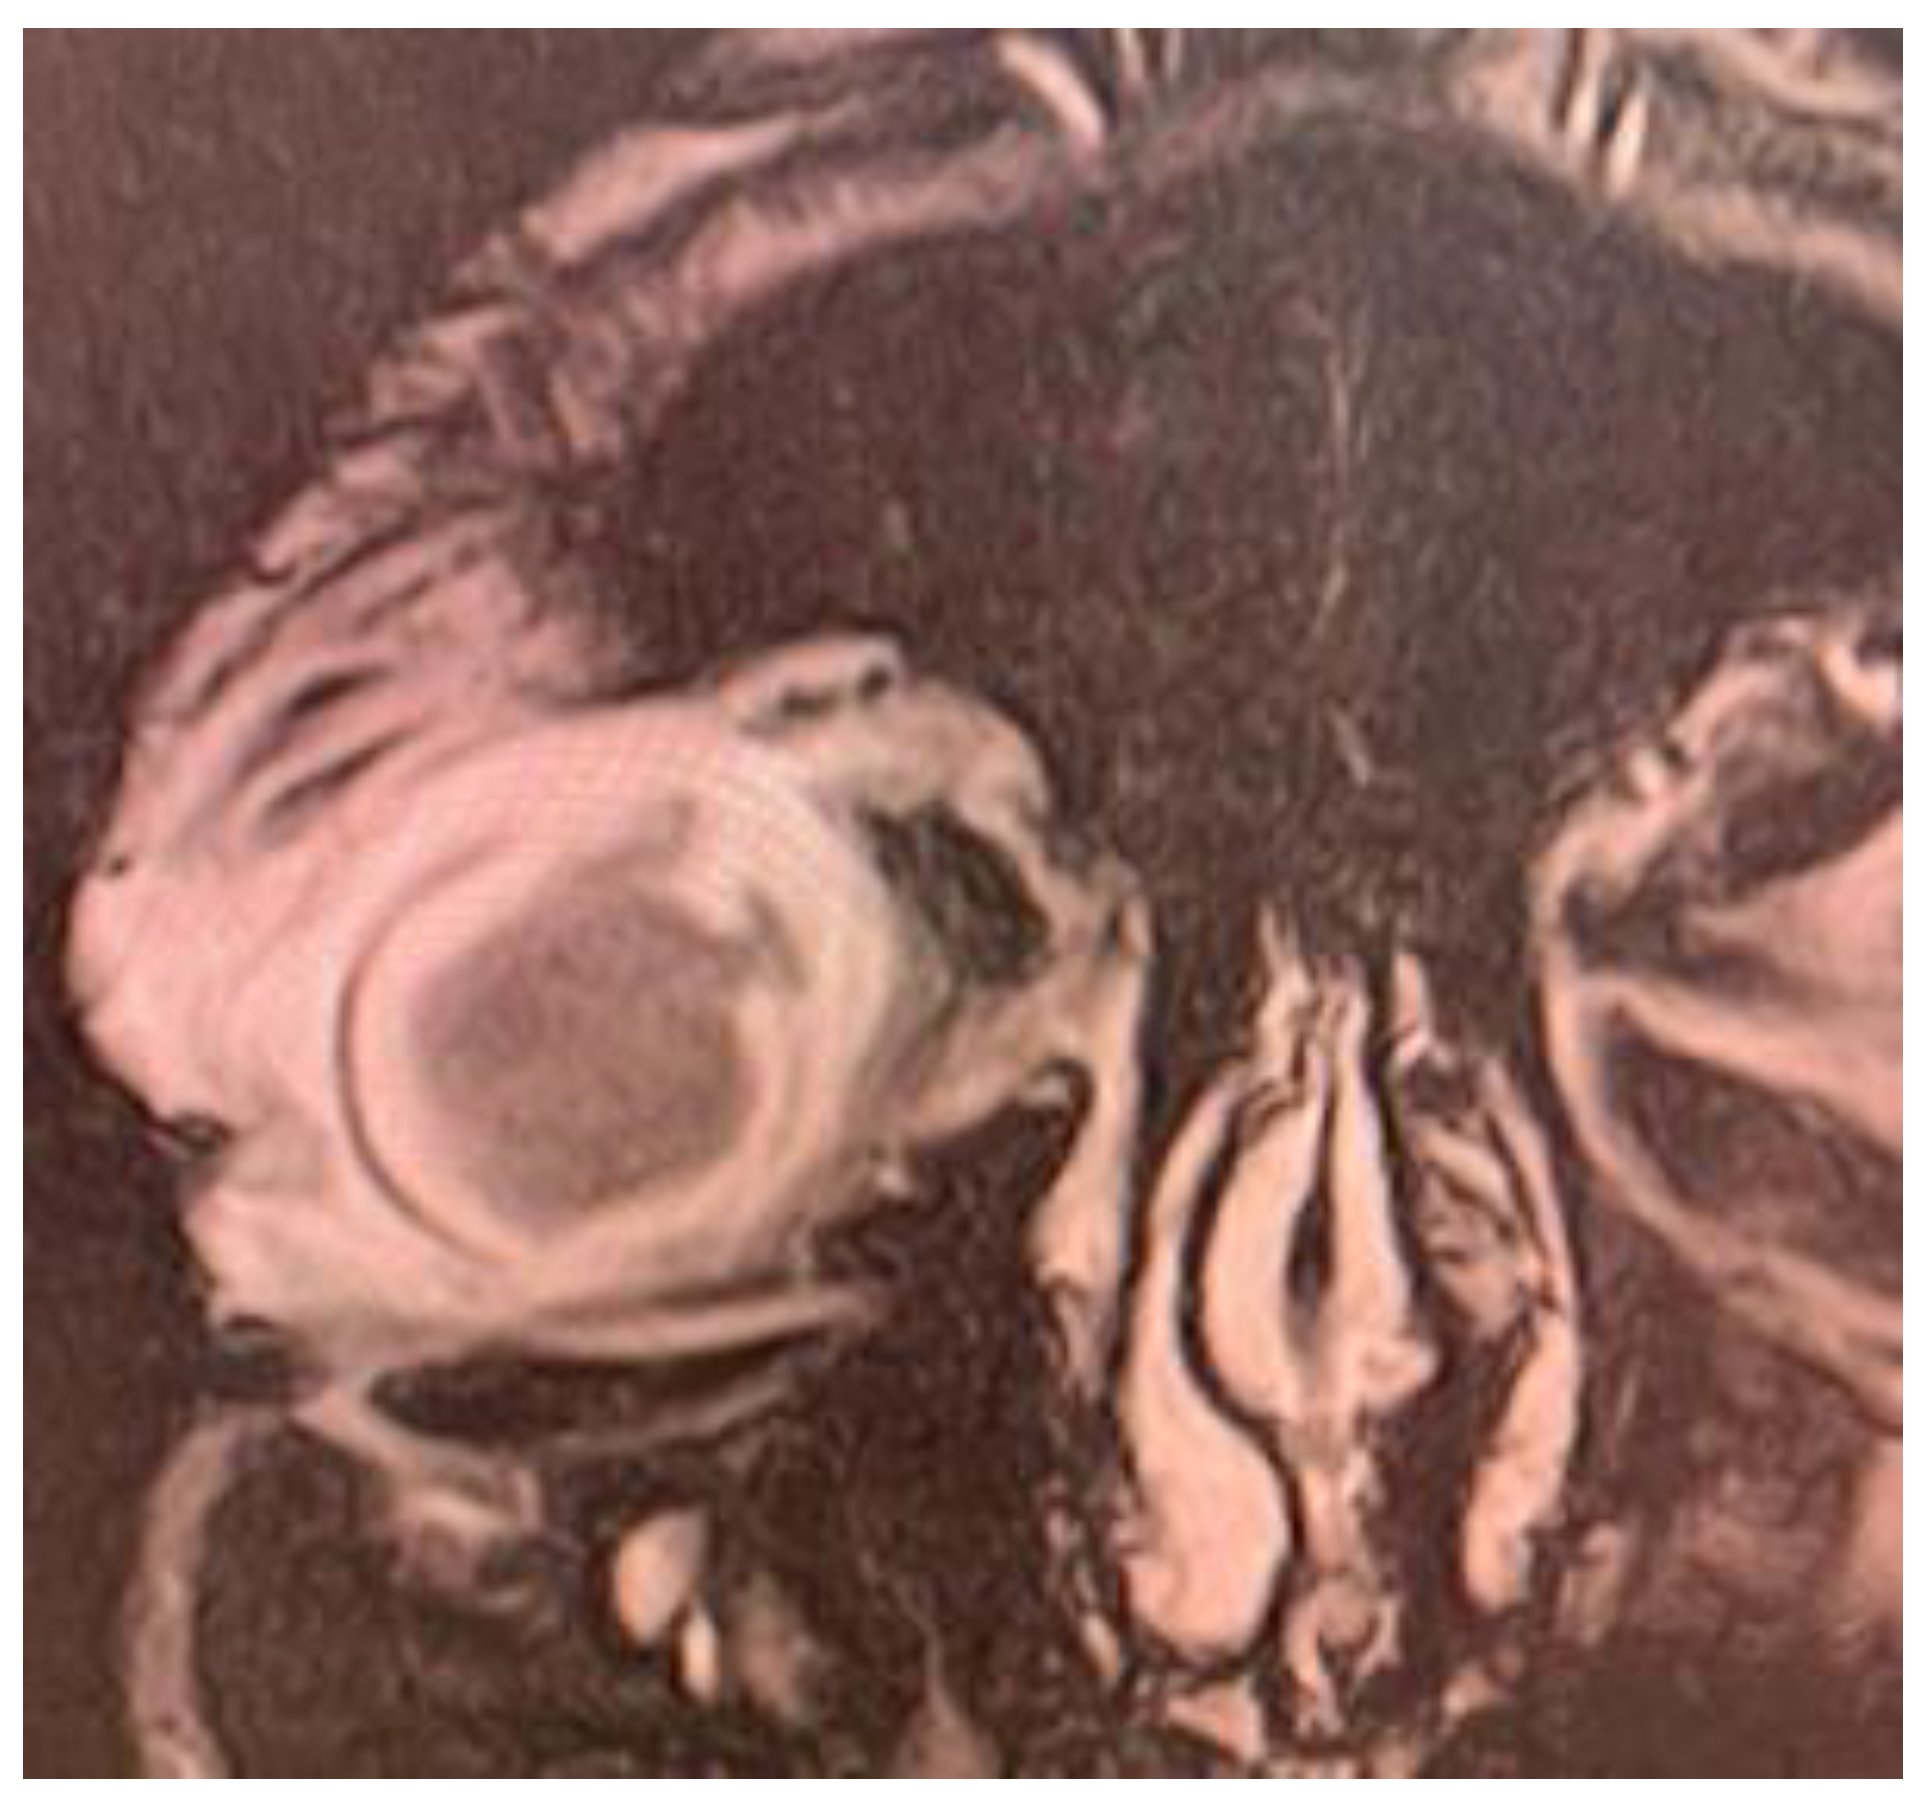

Magnetic resonance imaging (MRI) exam showed deformed right eyeball of reduced volume, with irregulated contour at the level of the medial convexity, at which level the scleral contour appeared interrupted, with underlying thickened choroid and vitreous body prolapse. Posterior lens luxation and increased hematogenous density of vitreous body were evidenced. Moderate inflammation of the preseptal and postseptal soft tissue was noticed (Figure 3).

Figure 3.

MRI exam: Right eye endophthalmitis with scleral abscess and perforation; increased density of vitreous body, deformed eye contour, with 2 area of scleral perforation in the superior and internal part; exophthalmia with inflammatory changes of the periorbital soft tissue.